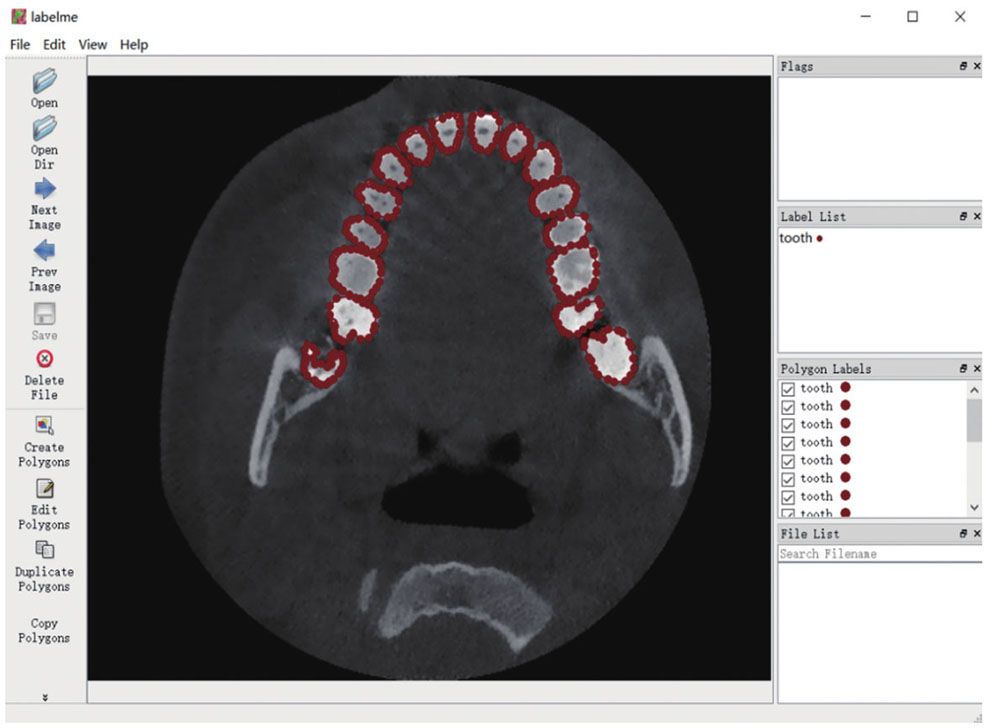

为了对数据进行训练,通过与口腔医院合作,在征得病人同意的情况下,采用CBCT医学图像扫描仪获取了10名病人的牙齿扫描DICOM格式的数据。为了便于之后的训练,本文将分辨率统一处理为256 pixel×256 pixel。然后,采用Labelme软件对训练图片进行标记。根据形态学对10名病人的口腔CBCT断层扫描图像进行手工标记,定义Label为Tooth,选取每4 frame标注一次,得到500 frame图片的数据。